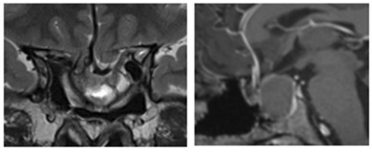

在法国巴黎的Lariboisiere大学医院,福洛里希教授制定了治疗方案。“第一步是经鼻内镜入路行视交叉“固定”术。第二步需切除肿瘤,并重建鞍底。防止肿瘤复发的同时,缓解目前视力下降的困境。”

术后一年,MRI显示肿瘤全切、脂肪填充空蝶鞍。术后左侧视野改善,视力稳定在0.3.右侧视力从0.03改善到1.0、如正常视力。

术后一年MRI